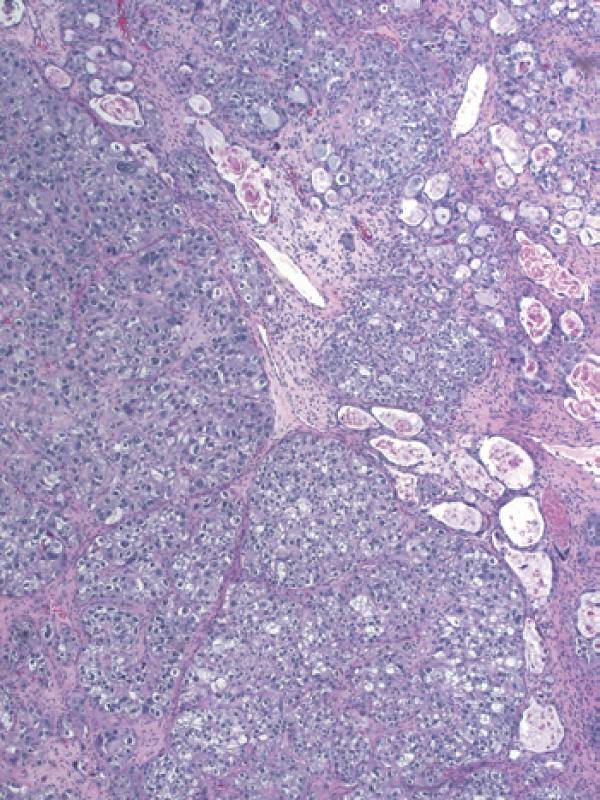

彩图4-4 典型混合细胞类型卵巢透明细胞癌,少量管状囊性结构(右上)与大量含透明细胞质的细胞结节样生长共存(左下)